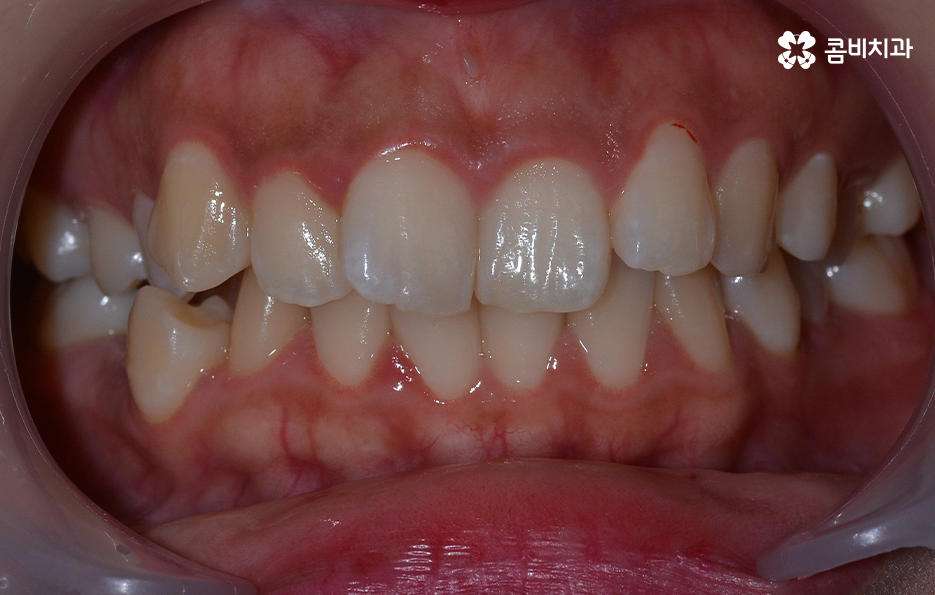

덧니는 윗니와 아랫니에 모두 있거나 앞니에 살짝 있는 수준의 덧니도 있으며 덧니가 심한 경우에는 개방교합으로 인해 입이 잘 다물어지지 않는 경우도 있기 때문에 덧니가 심한 정도에 따라서 치아교정의 계획은 세부적으로 달라질 수 있어요

덧니가 심하지 않은 경우에는 비발치로도 충분히 교정을 하는 경우도 있겠지만 덧니가 심한 경우에는 덧니 발치 교정을 통해서 치료가 진행되는 경우가 많이 있는데요. 그 이유는 치아교정의 원리를 생각하더라도 치아를 재배치하기 위해서는 기존의 치아가 움직일 공간이 필요한데 덧니는 치열이 이미 완성되고 있는 상태에서 치아가 나올 공간이 부족하여 덧니가 되는 경우가 많다는 점에서도 치아의 이동 공간을 확보하기 위한 발치가 필요할 수 있는 거예요

물론 치아의 이동 공간을 조금만 확보하면 되는 경우에는 악궁 확장이나 치간 삭제와 같은 방법으로도 치아의 이동 공간을 확보하여 비발치로 치아교정이 가능한 사례도 있지만 덧니 교정을 통해서 부정교합과 함께 얼굴형의 변화까지 치료 목적으로 하는 경우에는 발치가 필요한 경우가 많다고 볼 수 있어요